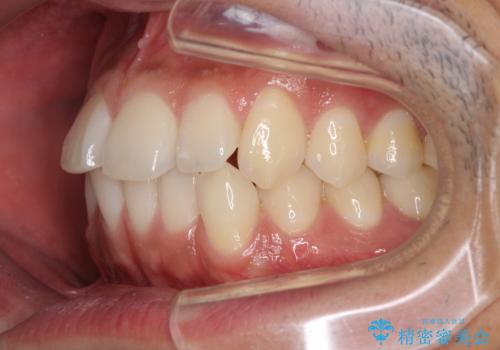

前歯のデコボコを治したい インビザライン矯正治療

- 前歯のデコボコを治したいとのことで来院された患者様です。

上下顎ともに歯列全体の後方移動とIPR(歯と歯の間を削る)によってデコボコが解消するように設計し、インビザラインにより治療を行うこととしました。

毎日22時間以上しっかりとマウスピースを装着していただいたので、スムーズに治療が進みました。歯と歯の間を削ることでうまくスペースコントロールでき、1年強で終えることができました。